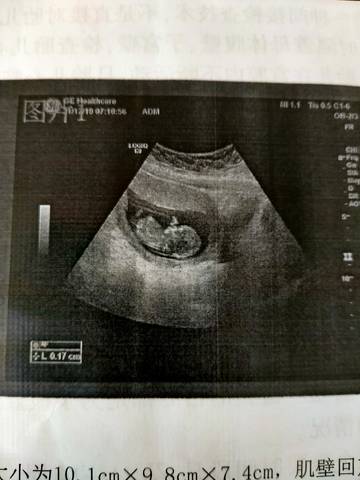

NT顺利通过大家帮忙看看是男宝宝还是女宝宝 我怎么感觉头有点大呢 哈哈

journal_insert_pic_1683584689journal_insert_pic_1683584705